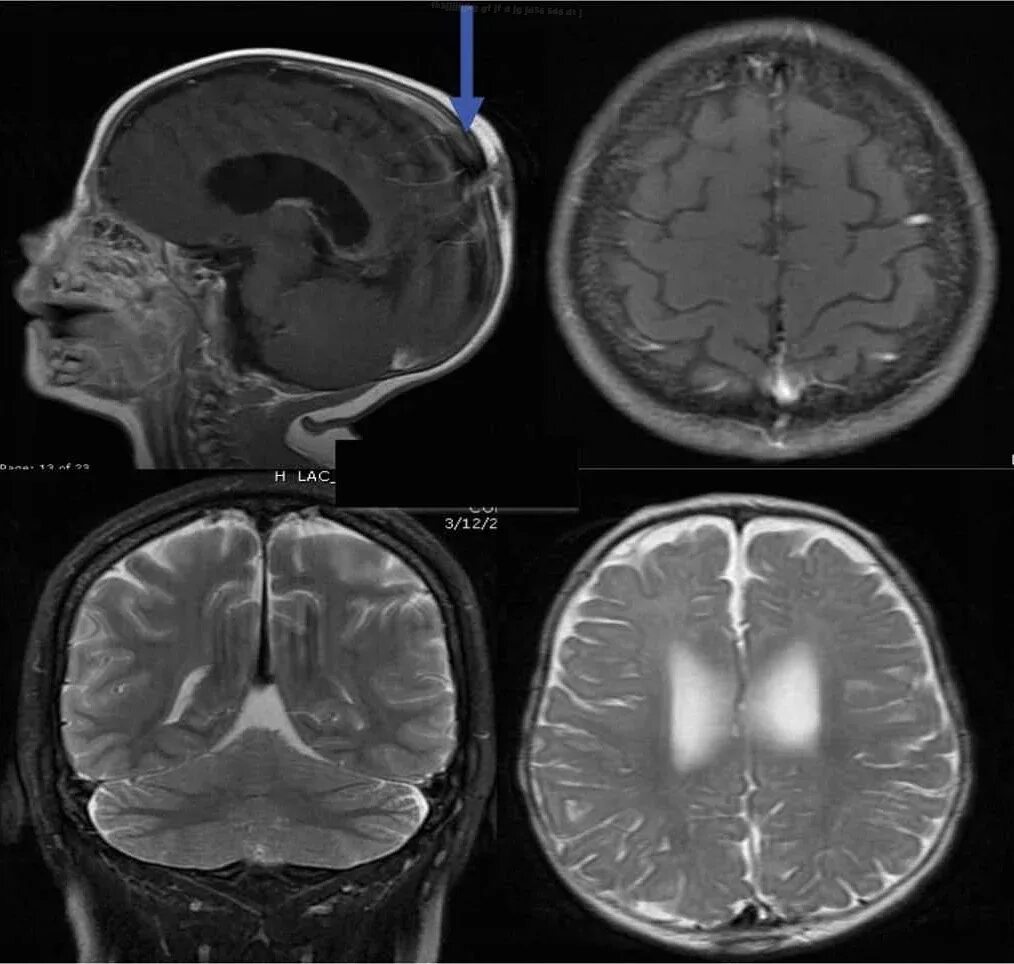

Чем отличается мрт от мрт с контрастом